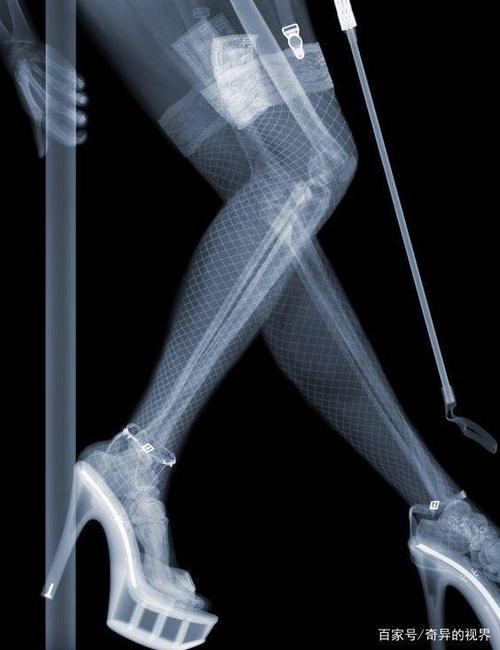

做x光检查是目前最为广泛的一个检查,医生使用的X射线可能会导致胎儿畸形,所以,至少需要1年后才可以怀孕,而且特别注意,预防x光检查中的电离辐射以及一些药物对胎儿的影响。而且,备孕期的女性需要做的检查还有很多,一些非处方药,那就需要在线下方和医生直接沟通。